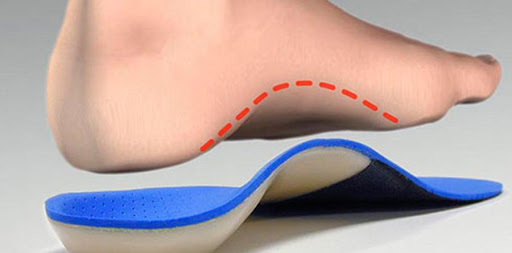

Тут все просто – это ортопедические стельки и страсбургский носок (будете гуглить слово «страсбургский», носок сразу после собора, пирога и суда).

Стельки разгружают своды стопы и фасцию вместе с ними за счет создания дополнительной опоры.